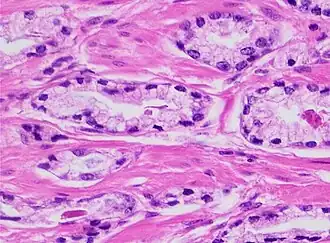

Architectural pattern of any suspicious cells, in this case nests of cells, as well as components of the intervening stroma.

Architectural pattern of any suspicious cells, in this case nests of cells, as well as components of the intervening stroma. -